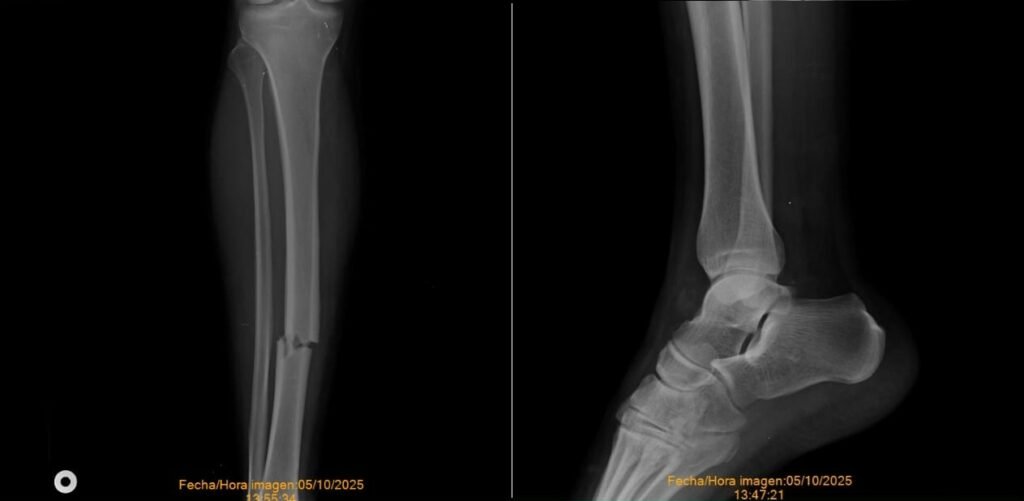

En diálogo con Lomas Conectado, la víctima, identificada como Martín Tarelli, de 28 años, contó que se dedica a realizar ventas y envíos en moto, y que el accidente le provocó graves lesiones. “Me chocó y me dejó en el UPA 1 de Fiorito, después se dio a la fuga sin dejar cédula, seguro ni nada. Me rompió la tibia, me hicieron 15 puntos en el tobillo y tengo muchos hematomas”, relató.

“Me dejó sin ingresos porque vendo cosas y no puedo moverme. No tengo obra social ni el dinero para los clavos. Me arruinó”, lamentó el joven, quien continúa recuperándose de las lesiones sufridas.